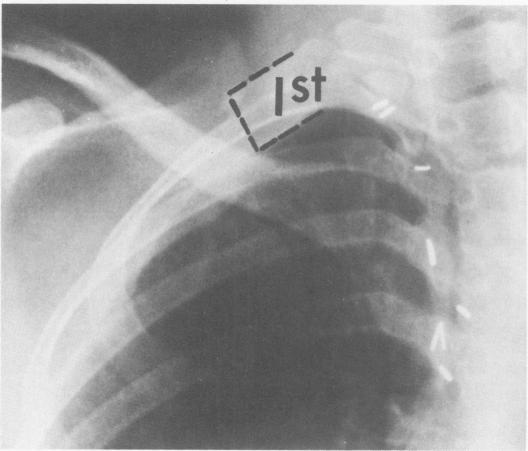

胸廓出口综合征的管理

Management of thoracic outlet syndrome.

This overall management program for thoracic outlet compression syndrome is based upon experience with 153 extremities in 149 patients and the results of others. The following conclusions are documented and discussed. 1) Diagnosis is based chiefly upon history; physical signs are inconstant and often absent. 2) Major vascular problems are unusual; angiography is not always necessary. 3) Electromyography is not always critical but does aid in diagnosis of carpal tunnel syndrome. 4) Non-operative treatment relieves most patients; operative decompression is indicated for a minority. 5) Transxillary first rib resection, with removal of cervical rib is the best operation. 6) Carpal tunnel decompression should be done concomitantly when needed. 7) Operation is relatively safe.

摘要

这个胸廓出口综合征的整体管理方案是基于对149例患者的153个肢体的经验以及其他研究结果制定的。以下结论得到了记录和讨论。1)诊断主要基于病史;体征不稳定且常不存在。2)主要血管问题不常见;血管造影并非总是必要的。3)肌电图并非总是关键的,但有助于诊断腕管综合征。4)非手术治疗可使大多数患者缓解;少数患者需要手术减压。5)经腋路第一肋切除术并切除颈肋是最佳手术方式。6)必要时应同时进行腕管减压术。7)手术相对安全。